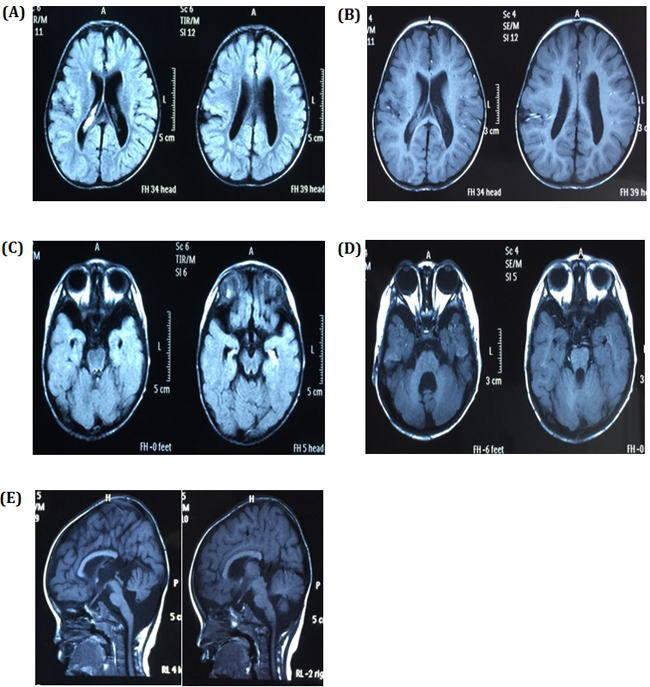

Our physical examinations showed that she was conscious but apathetic. She could not communicate verbally. Her height was 73 cm, and her weight was 6 kg. Her head circumference was only 43 cm, which is 86% of the normal range. She was hypomyotonic and had scoliosis. She had facial features typical of MCPH2 (Figure 1B), which manifest in a wide and low bridge of the nose, thick lips, broad eye distance, sloping forehead, high palate-maxillary arch and low-set and large ears. Brain imaging showed a slight expansion of bilateral brain ventricles, which was apparent on the left side; obvious expansion of the fourth ventricle; thinning of the corpus callosum with the absence of the splenium; dysplasia of the temporal lobe with small hippocampus, enlarged temporal horn and broadening lateral fissure; leukodystrophy, dysplasia of the white matter; and suspected schizencephaly in the right parietal lobe and slight atrophy of the brain stem and cerebellum. (Figure 2A-2E). Abdominal ultrasound examinations showed that her liver measured 1.6 cm under the ribs. Her kidneys were 4 x 2.2 cm on the right side and 3.8 x 2.3 cm on the left side.

Figure 2: Brain images A. and B. showing the expansion of bilateral brain ventricles, dysplasia of the brain white matter and suspicious schizencephaly in the right parietal lobe, C. dysplasia of the temporal lobe with small hippocampus and enlarge temporal horn, D. obvious expansion of the fourth ventricle and slight atrophy of cerebellum, and E. slight atrophy of the brain stem and thinning of the corpus callosum with absence of the splenium.